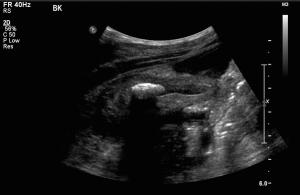

10-year-old male presents to the emergency department with left testicular pain and swelling for the last four days.